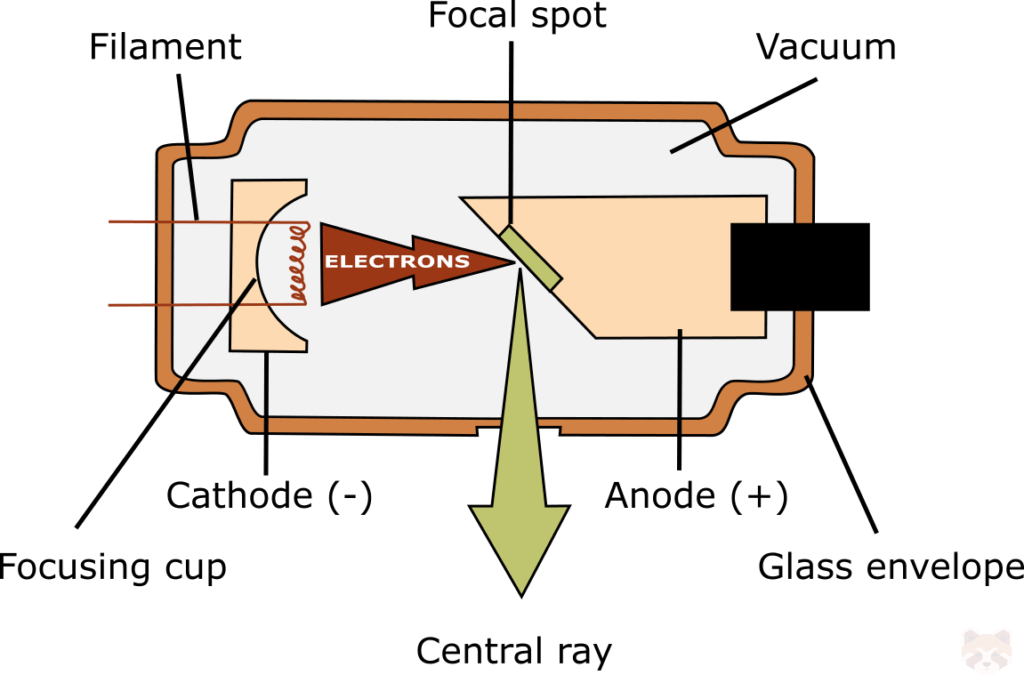

The dental x-ray unit tube is surrounded by a glass housing that holds a vacuum and sealed by an aluminum or plastic frame. The glass prevents radiation from escaping. The x-ray source consists of two electrodes, the anode (positive) and cathode (negative). The cathode filament is heated up to emit electrons which are accelerated toward anode by applying a 20–200 kV potential in a vacuumized x-ray tube. A focusing cup magnetically focuses the electrons into a narrow beam directed at a small area on the anode (focal spot). Between the cathode and anode is a tungsten target, which when hit produces x-rays. This process produces an enormous amount of heat. The vacuum prevents combustion and provides a clean environment for electron conduction.

The focal spot refers to the area on the anode (tungsten wire) hit by electrons to produce x-rays. The focal spot can also be referred to as the target. The size of the tungsten target ranges from 0.5-1.0mm and is a set parameter of the device (cannot be changed). The smaller the focal spot, the sharper the image.